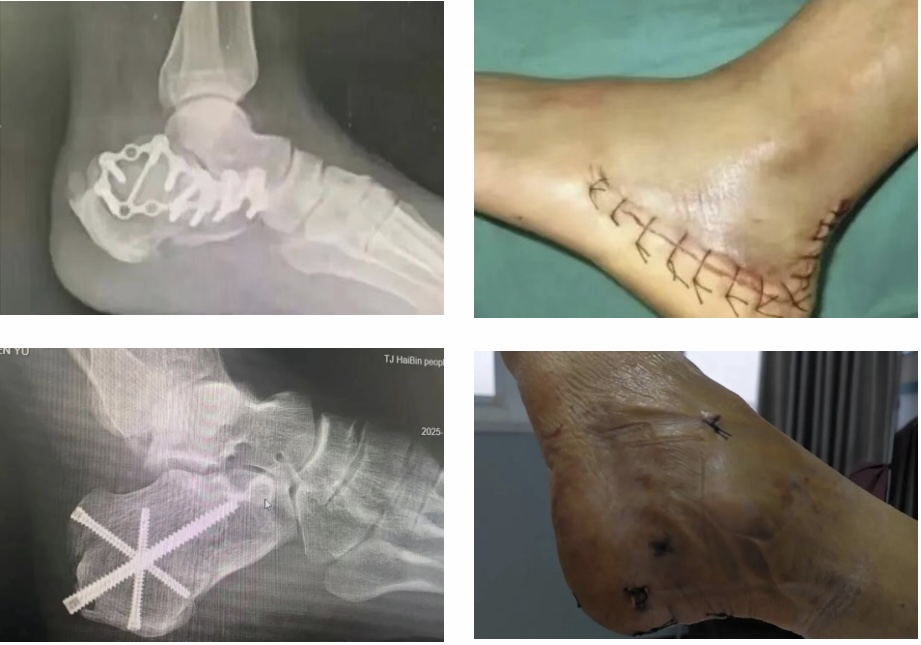

近日,骨二科成功为一名高处坠落导致跟骨严重骨折的患者,实施首例跟骨骨折闭合复位空心钉固定微创手术。

患者为中年男性,因高处坠落导致跟骨严重骨折,影像检查显示其跟骨高度降低、宽度增宽。以往,这类骨折通常采用传统的“大L型”切开手术,不仅切口长、创伤大,还存在伤口愈合难、感染风险高、易发生并发症等问题,给患者带来身心双重负担。

为最大限度减少创伤、提升康复效果,骨二科王来旭主任带领团队仔细评估,决定采用目前先进的闭合复位空心钉固定微创术式。术中,手术团队仅通过数个微小切口,在避免大面积切开的情况下,精准完成了骨折复位与内固定操作。

据王来旭主任介绍,与传统开放手术相比,该微创技术创伤小,仅通过微小切口完成操作,极大保护了足部软组织完整性,有效避免了术后伤口感染、皮肤坏死等并发症。为患者早期开展康复锻炼创造条件,有助于缩短住院及整体康复时间。